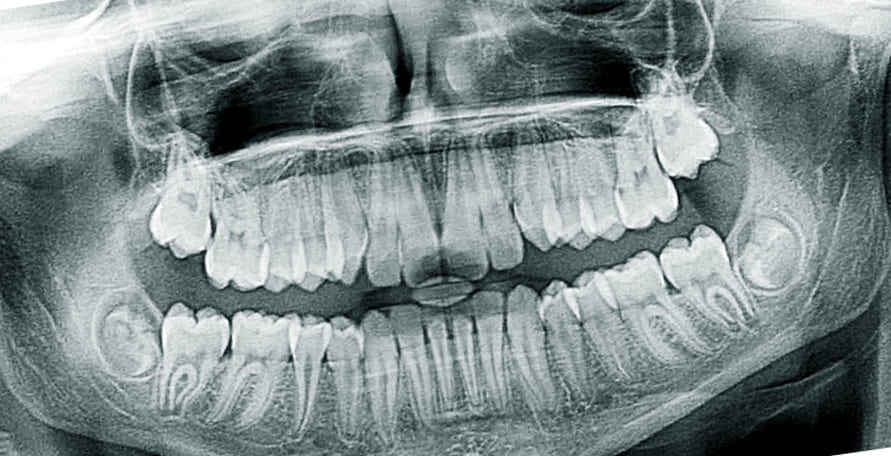

나이가 들면서 치아가 수명은 다하는 것은 당연합니다. 과거에는 빠진 치아를 틀니로 대체하였지만 최근에는 임플란트 시술을 통해 빠진 이를 새로 채웁니다.

앞니 임플란트를 하기 전 임시치아를 하는데 기존 치아와 모양이 굉장히 흡사하고 씹는데는 큰 지장이 없어서 아마 불편함은 없을 것입니다. 또한 임플란트 시술이 보편화되고 고도화됨에 따라 임시치아를 하는 기간이 굉장히 짧아졌으므로 조금 어색함과 이질감이 들더라도 잠깐 동안만 한다고 생각하고 빨리 적응하길 바랍니다.

최근에는 3차원 CT스캔을 이용해 자신의 치아 상태에 최적화된 임플란트를 만들 수 있을정도로 꼼꼼한 진단과 세심할 시술이 가능하니 적응할 수 있을까 라는 걱정은 하지 않아도 됩니다.